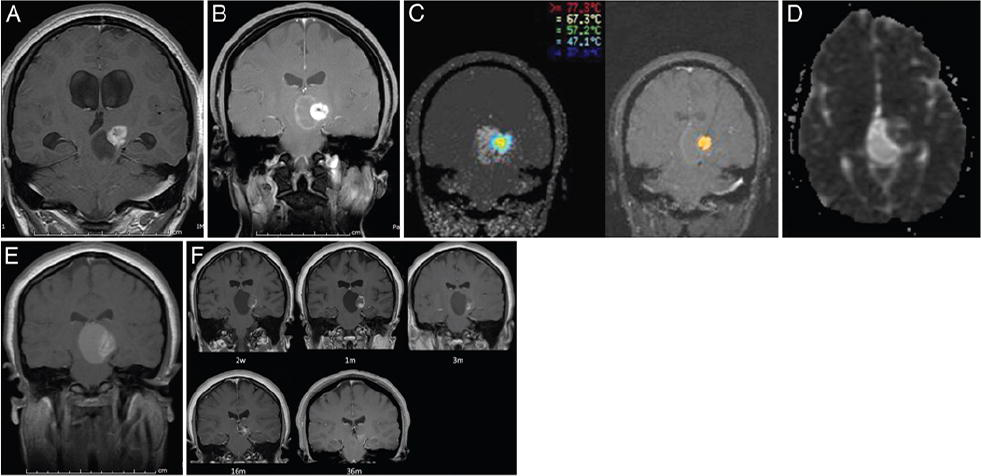

一名17岁女孩出现头痛和钙化的中脑丘脑毛细血管星形细胞瘤。这是我们系列中一次使用MRgLITT的情况,涉及较长的随访时间。另外,迄今为止,这是用LITT治疗的囊性毛细胞星形细胞瘤的病例。图A显示了患者呈现的T1加权对比增强MR图像。首先对她进行了内镜三脑室造口术,囊肿开窗术和活检(图B),然后进行MRgLITT(图C)治疗。消融当天进行的术后MRI证实了Hawasli等所描述的预期变化,该变化由治疗区边缘的扩散限制环组成(图D)是新的造影剂环,肿瘤周围水肿,并且在这种情况下,病灶尺寸意外增加(图E)。2周后,腹膜和囊肿水肿减少,新的增强边缘随时间减少(图F)。在36个月的较后一次随访中,该无症状患者未复发。

A:初始MR图像显示左丘脑/丘脑毛细胞星形细胞瘤,其囊性成分为29×23×23 mm,相关的异质固体成分为17×17×15 mm。肿瘤引起阻塞性脑积水。较初对患者进行了内窥镜三脑室造口术,囊肿开窗术和活检。B:较初的内窥镜干预后六个月,经消融T1加权MRI并进行Gd增强,显示左丘脑/丘脑的固体成分为20×18 mm。C: LITT热图和不可逆损伤估计的术中图像。D:消融当天的MR图像显示消融肿瘤边缘处的扩散限制环。E:消融后T1加权对比增强MR图像显示消融区域增强,肿瘤周围水肿和有趣的囊肿增大。F:在2周和1、3、16和36个月时进行对比的随访T1加权MR图像。消融后6个月,患者再次进行内镜下囊肿开窗术。